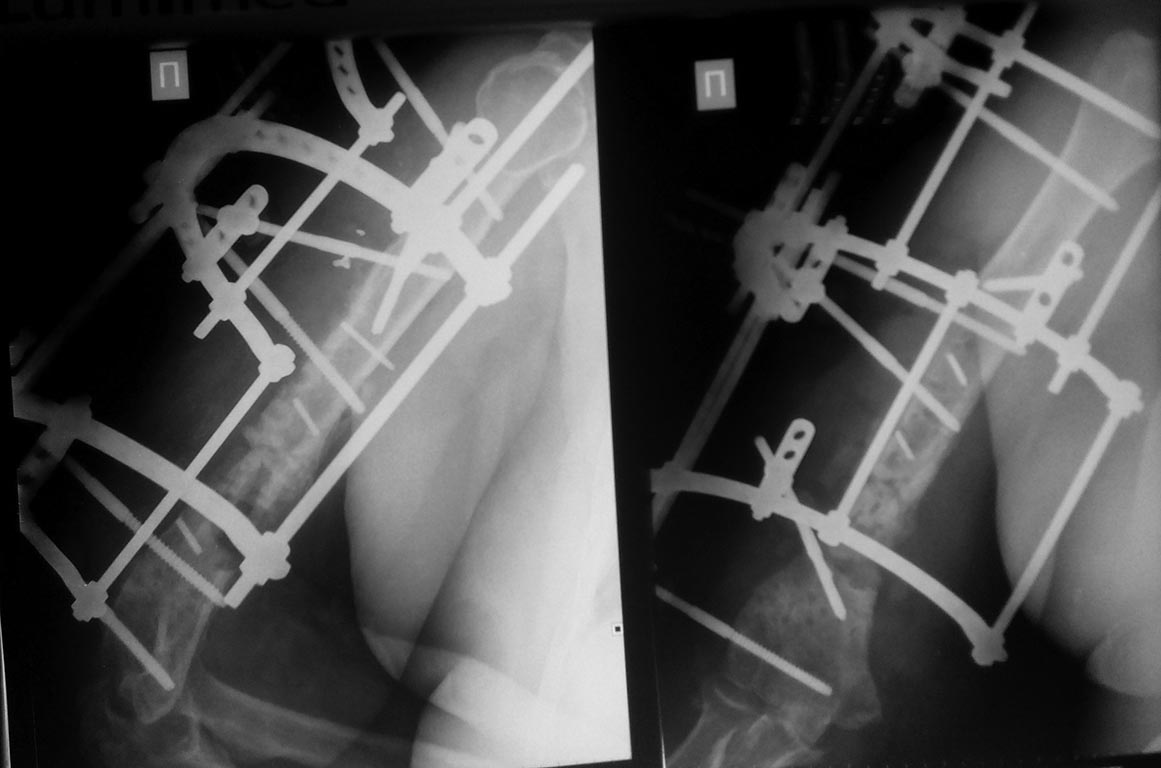

[Ortho] Реостеосинтез плеча. Что дальше...?

2 месяца с АВФ